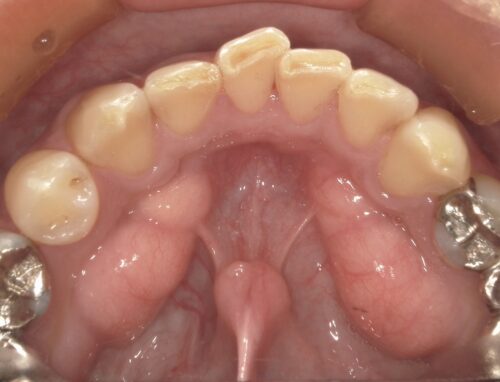

突然ですが、歯茎にこの様なコブができていませんか?

皆様もお口の中を確認してみてください。

このコブの正体は“骨隆起”といいます。

“骨隆起”とは、顎の骨が過剰に成長することにより、歯茎などの表面上に骨がボコッと盛り上がった状態をいいます。